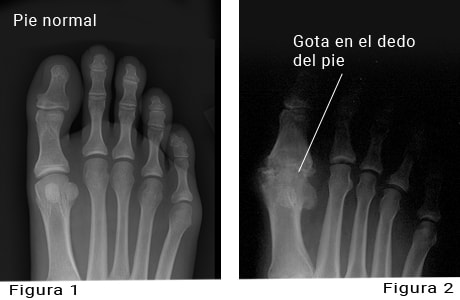

Imágenes radiográficas de un pie normal y un pie con gota en el dedo gordo del pie

Imagen por cortesía de Paul Traughber, M.D., Boise, Idaho.

La figura 1 es una radiografía de un pie normal con huesos y articulaciones sanos.

La figura 2 es una radiografía de una articulación del dedo del pie deformada a causa de gota crónica.